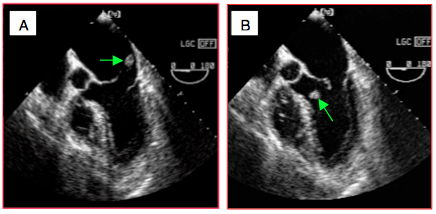

Figure 26.24 : Rupture ischémique totale d'un muscle papillaire. On aperçoit un fragment de pilier à l’extrémité de cordages, flottant dans l’OG en systole (A) et dans le VG en diastole (B). L’orifice de régurgitation est si grand et la dysfonction du VG si profonde que la Vmax de l’IM est basse (1-1.5 m/s) ; le flux Doppler couleur est laminaire en diastole et en systole, seule sa couleur change.